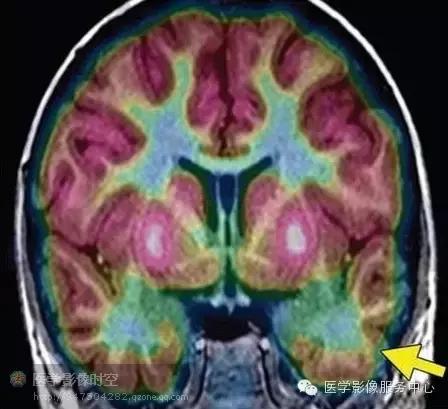

MR-PET融合图像通过软件配合MR图像和PET图像来实现。两组数据独立采集,但是病人摆位上需要类似,以便于图像配准。该技术可以直接关联MR发现的结构上的异常与PET发现的代谢异常。在发作间期,代谢异常的区域表现为低代谢,而在发作期,病变表现为高代谢。很多在常规磁共振上容易忽略的轻微异常,在融合图像上表现更加突出。

图1b 冠状MR-PET融合图像显示左侧颞叶前部的局部低代谢区。

图2b横断MR-PET融合图像显示局部低代谢(箭)。病理学检查显示ⅡB型局部皮质发育不良。

局部皮质发育不良的影像学表现可以非常轻微,仅靠磁共振成像容易漏诊。MR-PET融合图像和磁源成像有助于定位磁共振成像所见的轻微结构异常和异常信号。发作间期PET检查可以显示局部皮质发育不良累及皮层区显示为低代谢(图1,3-5)。发作间期磁源成像显示局部皮质发育不良的脑皮层癫痫样放电灶(图3a,4b)